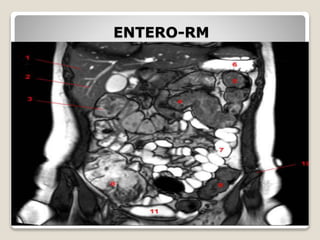

ENTERO-RM

ENTERITE REGIONAL

–Enterite Segmentar ou Doença de Crohn;

–uma doença inflamatória crônica de etiologia

desconhecida que envolve qualquer porção do

trato GI, mas que comumente acomete o íleo

terminal, com fibrose e espessamento da

parede intestinal.